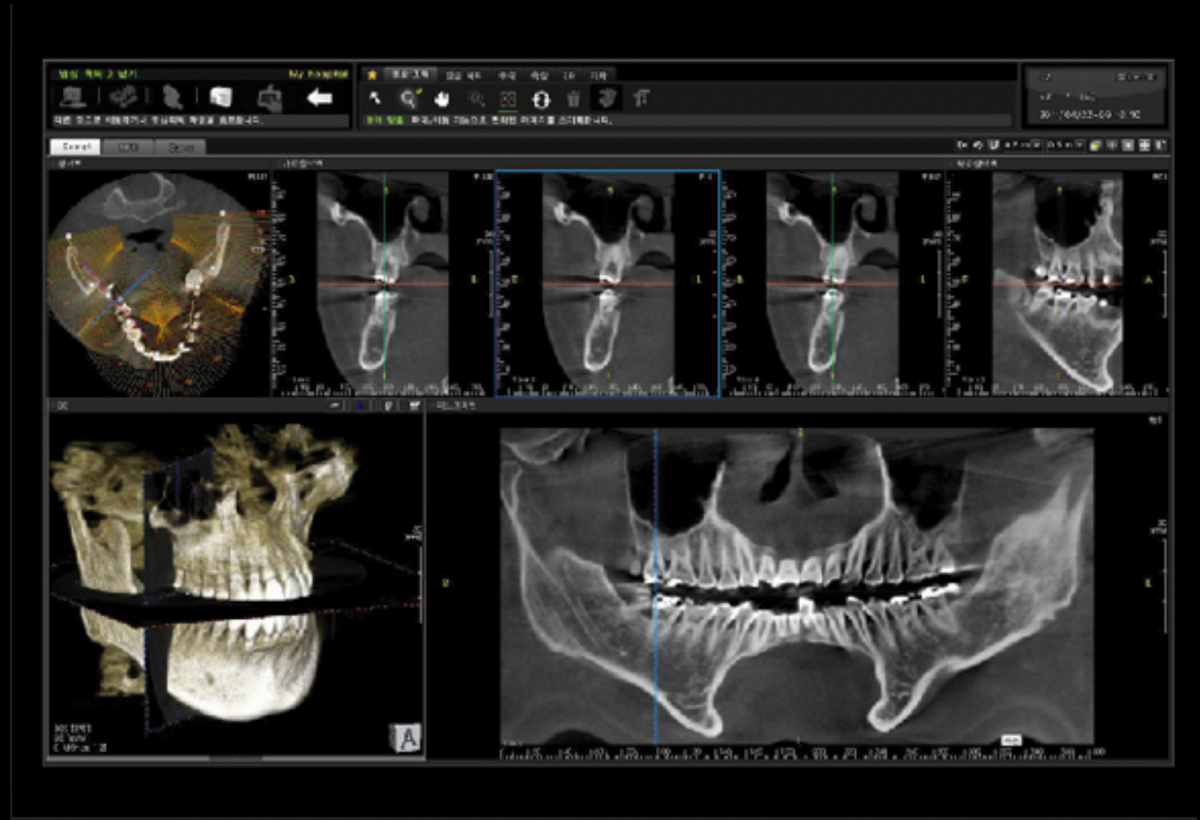

Современные 3D-томографы обладают возможность проводить не только трехмерные, но и двухмерные исследования, которые решают повседневные задачи на стоматологическом приеме. Любой рентгенологический метод показан только по показаниям, поэтому на современном этапе развития медицины, и в частности стоматологии, важно назначать пациентов на лучевую диагностику опираясь на правила нормированности и обосновываемости. Поэтому Papaya 3D позволяет получить помимо КТ, также панорамную зонографию челюсти (ортопантомограмму, ОПТГ) и телерентгенограмму (ТРГ). ОПТГ является классическим вариантом на первичной консультации пациента и для составления общего плана лечения. ТРГ же является незаменимым в протоколе ортодонтической подготовки.

• панорамный реформат. Возможность постройки классической и сегментарной панорамы позволяет продемонстрировать план лечения пациенту, а также оценить расположение анатомических структур на боковых кросс-секциях.

• модуль дентальной имплантации. Возможность виртуальной установки дентального имплантата с анализом окружающей костной ткани. В библиотеке представлен широкий спектр имплантологических систем с индивидуальной прорисовкой имплантата.

• выделение нижнечелюстного канала позволяет продемонстрировать расположение важного анатомического образования и определить зону безопасности при проведении лечения.